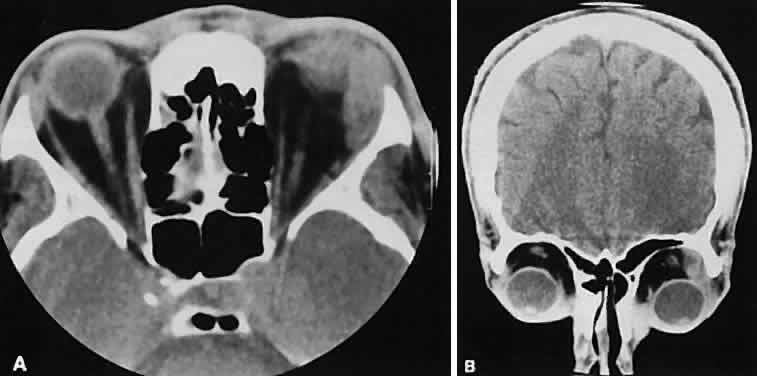

| Abnormal size of the optic nerve and sheath on the CT scan usually is pathologic. Rothfus

and colleagues49 suggested a differential approach based on high-resolution CT morphology. An enlarged optic nerve also is associated with an age-related differential diagnosis. Most gliomas are found in children, whereas optic nerve sheath meningiomas tend to afflict adults, primarily women. Nevertheless, there are exceptions for each. Optic nerve gliomas are associated with neurofibromatosis. A prospective study determined that a child with known neurofibromatosis has a 15% chance of having a glioma of the anterior visual pathway. Conversely, a child with an optic nerve glioma has a 25% chance of having neurofibromatosis.50 Although an optic nerve meningioma can occur in association with neurofibromatosis, particu-larly NF-2,51 the association is not as firmly established as with gliomas. It is uncommon but well-established that optic nerve meningiomas can occur during childhood. Not only can they create confusion regarding differentiation from optic nerve glioma, but, most important, they behave in a more aggressive fashion.52 The CT evaluation of optic nerve lesions is facilitated by the use of 1.5-mm axial slices and intravenous contrast.49 Gliomas usually appear as a fusiform enlargement with sharp delineation from the surrounding tissue due to circumscription by an intact dura (Fig. 10). Kinking and buckling of the optic nerve along with infarctive cysts are typical findings in an optic nerve glioma. Bilaterality and intracranial involvement of the anterior visual pathway also may be noted. The radiographic signature of an optic nerve meningioma is more variable (Fig. 11). The optic nerve shadow tends to be diffusely enlarged, with irregular expansion along the optic nerve. Jakobiec and colleagues53 found diffuse enlargement of the optic nerve with apical expansion to be the most frequent pattern. Calcification within the optic nerve shadow, which is unusual in optic nerve gliomas, is common with optic nerve meningioma. The irregular excrescent margins most likely signify extradural invasion into the adjacent orbital soft tissues. A central linear lucency extending the length of the optic nerve shadow also is a typical finding of an optic nerve meningioma.49 These two lesions represent the most frequent tumors affecting the optic nerve. Other reported tumors include hemangioblastoma, leukemic infiltration, and involvement by metastatic disease. Enlargement of the dural sheath around the optic nerve, an optic nerve meningocele, can be confused with a tumor.54 The radiographic procedure of choice for evaluating suspected optic nerve lesions is MRI with gadolinium and high-resolution, fat-suppression techniques. ORBITAL TUMORS In a patient with an orbital mass, CT can show not only the mass but also other valuable information such as shape, location, consistency, intralesional calcium, and effect on surrounding structures.55 Contrast enhancement offers some ideas about vascularity. VASCULAR TUMORS The vascular tumors under consideration are capillary hemangioma, cavernous hemangioma, lymphangioma, and hemangiopericytoma. Capillary hem-angiomas and lymphangiomas are benign infiltrativetumors seen in a pediatric population. Capillary hemangiomas have a homogeneous consistency, display intense uniform contrast enhancement, and do not usually displace any orbital structures (Fig. 12). Phleboliths are a characteristic finding in hemangiomas and, when present, are virtually pathognomonic of this diagnosis.56 Lymphangiomas have a cystic component, which, on occasion, may hemorrhage into itself, accounting for rapid onset of symptoms and clinical/radiographic evidence of mass effect (Fig. 13). In all likelihood, scans require sedation for an adequate study. Thin (1.5-mm) axial views with computer reformatting for coronal views along with contrast enhancement should provide an adequate study.

Both cavernous hemangiomas (Fig. 14) and hemangiopericytomas typically are seen in adults. Their radiographic appearance is similar and shows a well-demarcated, contrast-enhancing mass, although more intense enhancement may be seen with the hemangiopericytoma. The differential diagnosis of a well-demarcated, contrast-enhancing lesion is listed in Table 3.